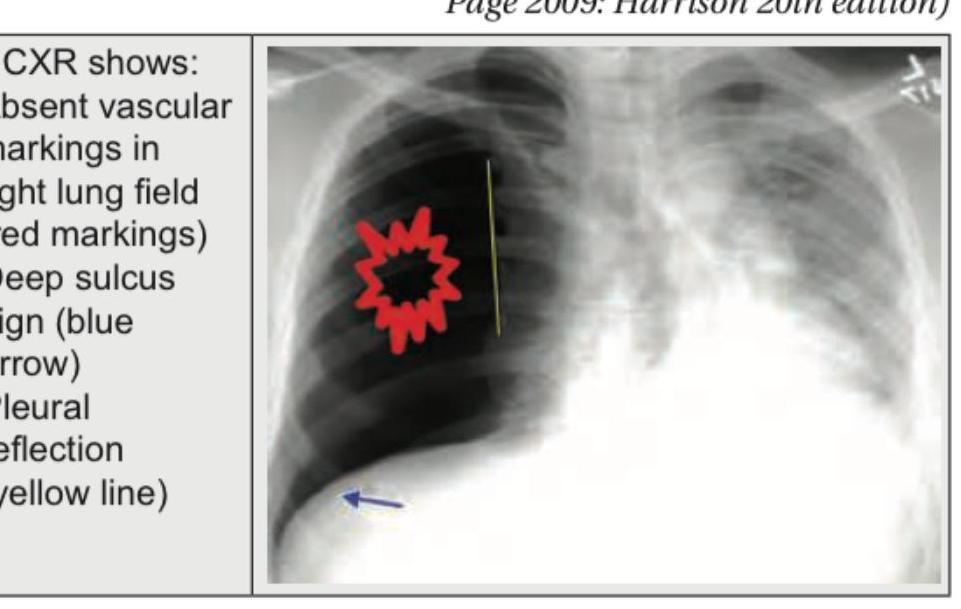

A 45-year-old male presents with sudden onset shortness of breath and chest pain. A chest X-ray is obtained. What is the most likely diagnosis based on the image?

Explanation: ***Pneumothorax*** - The chest X-ray shows several classic signs of a pneumothorax: **absent vascular markings** in the right lung field (indicated by red markings), a **deep sulcus sign** (blue arrow), and a visible **visceral pleural line** (yellow line) separating the collapsed lung from the chest wall. - The sudden onset of **shortness of breath** and **chest pain** in a 45-year-old male is consistent with the clinical presentation of a spontaneous pneumothorax. *Pleural Effusion* - A pleural effusion would typically present as a **blunting of the costophrenic angle** and a **meniscus sign** (concave upper border of fluid), which are not the primary features seen here. - While fluid can cause chest pain and shortness of breath, the distinct visceral pleural line and absent lung markings point away from an effusion as the primary diagnosis. *Pulmonary Edema* - Pulmonary edema is characterized by **cardiomegaly**, **perihilar haziness**, **Kerley B lines**, and often **bilateral effusions**, none of which are evident on this X-ray. - The clear lung field with absent markings is contrary to the diffuse alveolar or interstitial opacities seen in pulmonary edema. *Consolidation* - Consolidation, typically due to pneumonia, shows as a **lobar or segmental opacification** with **air bronchograms**, indicating fluid or cells filling the alveoli while the airways remain open. - This image clearly demonstrates a collapsed lung with air in the pleural space, not opacified lung tissue or air bronchograms.